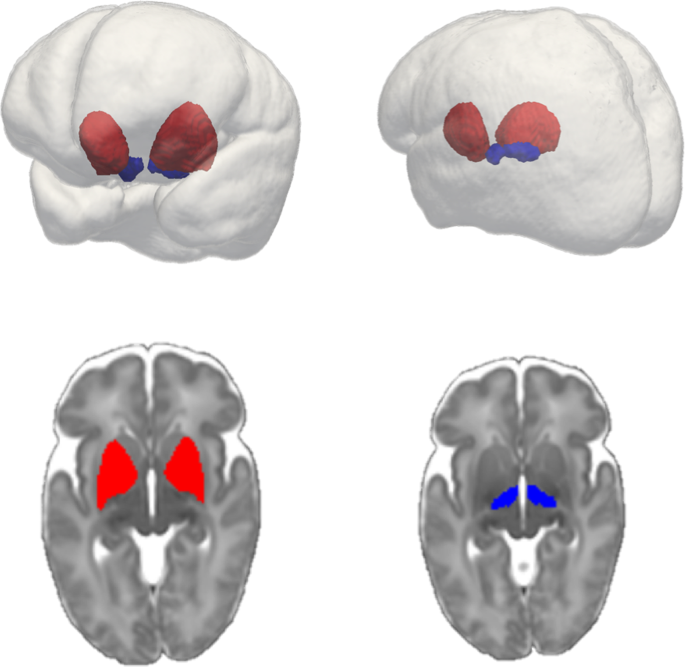

The psychiatric PRS predicted subthalamic and lentiform nucleus volumes in preterm infants in both the full mixed-ancestral cohort and the sub-sample of European infants. The subthalamic and lentiform nuclei are shown in Fig. 1. For the full, mixed-ancestry cohort, the psychiatric PRS was negatively associated with lentiform nuclear volume (β = −0.24, p = 8 × 10−4, R2 = 0.057, (pT = 0.1)); the PRS also showed a modest negative association with subthalamic nuclear volume (β = −0.18, p = 0.01, R2 = 0.032, (pT = 0.05)) which did not survive multiple testing correction (Table 2 and Fig. 2a and b). In the sub-sample of European infants, the psychiatric PRS was negatively associated with lentiform nuclear volume (β = −0.24, p = 8 × 10−3, R2 = 0.056, (pT = 0.1)) and subthalamic nuclear volume (β = −0.26, p = 3 × 10−3, R2 = 0.069, (pT = 0.05)) (Table 3 and Fig. 2c and d). For all associations with a p value < 0.05, the direction of the association was negative, that is, larger psychiatric genetic risk scores were associated with smaller deep grey matter volume. No association was found between the PRS and caudate or thalamic volume for either the full mixed-ancestral sample or the sub-sample of European infants (Tables 2 and 3). We note that these results remain robust if we correct the deep grey matter volumes for a more extended list of covariates that includes postmenstrual age at scan, gender and birth weight in addition to gestational age at birth and brain volume.

Subthalamic nucleus (blue) and Lentiform nucleus (red) within glass brain (top right and top left). Lentiform nucleus (bottom left) and subthalamic nucleus (bottom right) overlayed on 40-week neonatal template (axial cut).